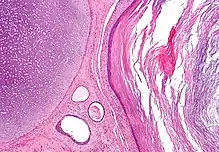

A mature teratoma is a grade 0 teratoma. They are highly variable in form and histology, and may be solid, cystic, or a combination of the two. A mature teratoma often contains several different types of tissue such as skin, muscle, and bone. Skin may surround a cyst and grow abundant hair (see dermoid cyst). Mature teratomas generally are benign, with 0.17-2% of mature cystic teratomas becoming malignant.[16]

A dermoid cyst is a mature cystic teratoma containing hair (sometimes very abundant) and other structures characteristic of normal skin and other tissues derived from the ectoderm. The term is most often applied to teratoma on the skull sutures and in the ovaries of females.

Regardless of location in the body, a teratoma is classified according to a cancer staging system. This indicates whether chemotherapy or radiation therapy may be needed in addition to surgery. Teratomas commonly are classified using the Gonzalez-Crussi[18] grading system: 0 or mature (benign); 1 or immature, probably benign; 2 or immature, possibly malignant (cancerous); and 3 or frankly malignant. If frankly malignant, the tumor is a cancer for which additional cancer staging applies.

Teratomas are also classified by their content; a solid teratoma contains only tissues (perhaps including more complex structures); a cystic teratoma contains only pockets of fluid or semifluid such as cerebrospinal fluid, sebum, or fat; a mixed teratoma contains both solid and cystic parts. Cystic teratomas usually are grade 0 and, conversely, grade 0 teratomas usually are cystic.